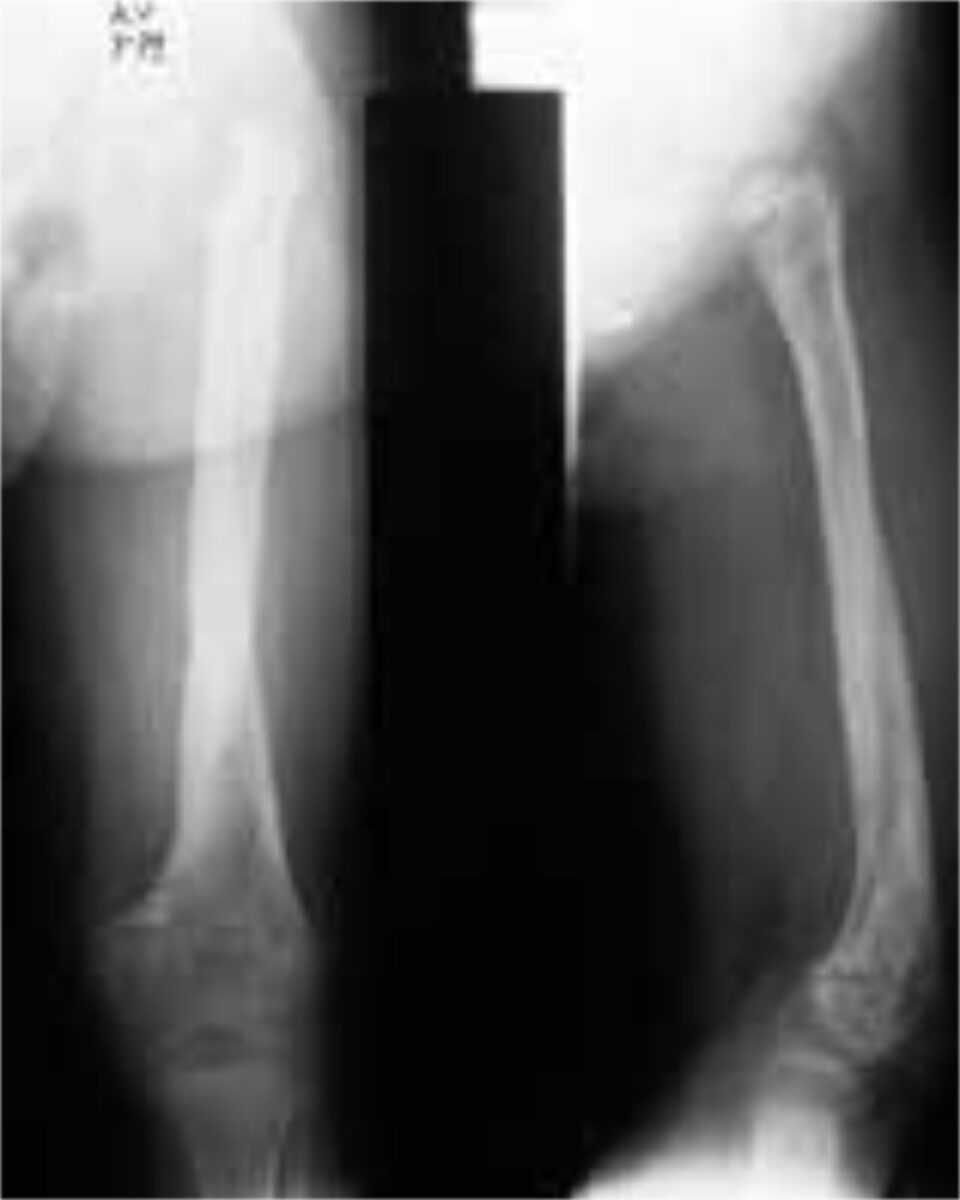

Chronic osteomyelitis arises as a result of inadequate treatment, and is already established after 36 hours. The tibia is most often involved, followed closely by the femur. The periosteum will form an envelope of living bone (Figure 1), the involucrum, around the medullary space in order to separate it from the rest of the bone. This envelope thus prevents the dispersion of infected emboli throughout the body, but at the same time also prevents antibiotics to pen-etrate into the marrow. The involucrum bridges the infected area, thus allowing safe removal of all necrotic bone and sequestra. Osteomyelitis lasts a life-time, because one is never sure that it is completely eradicated. Long remissions can alternate with periods of exacerba-tion. The term “years without relapse” is therefore more accurate than the term “cure”. Differential diagnosis should always include TBC, Ewing sarcoma and Sickle Cell disease. A fistula can always lead to malignant degeneration.